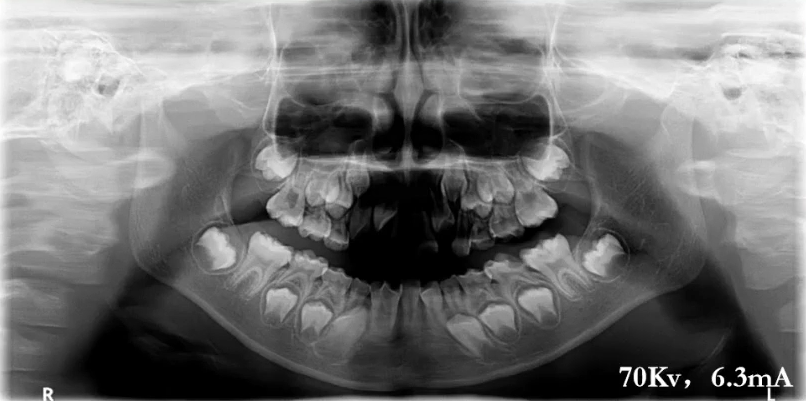

上颌前牙区、下颌前牙区牙位辨认

患者处于混合牙列期,可以看到右侧前牙区有多生牙,下颌有融合牙的存在。